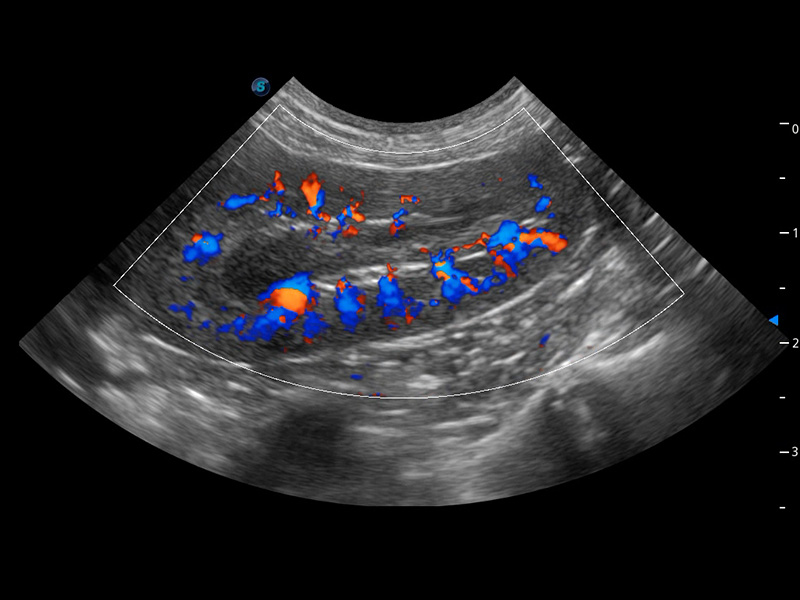

ProPet 60 作為一款高端臺式動物超聲設備,為動物醫(yī)生的日常診斷提供了一系列貼合動物臨床需求、解決臨床實際問題的高級成像功能。憑借全系列高清探頭,滿足醫(yī)生對腹部、心臟、生殖、淺表、肌骨等成像的所有需求,切實幫助您提升檢查效率,提高診斷信心。